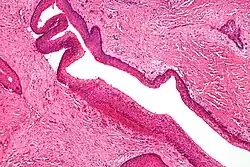

Micrograph showing keratocystic odontogenic tumour, a common finding in nevoid basal cell carcinoma syndrome. H&E stain.

Nevoid basal cell carcinoma syndrome

Nevoid basal cell carcinoma syndrome, also known as Gorlin syndrome, is an autosomal dominant cancer syndrome in which the risk of basal cell carcinoma is very high. The disease is characterized by basal cell nevi, jaw keratocysts and skeletal abnormalities. Estimates of nevoid basal cell carcinoma syndrome prevalence varies, but is approximately 1 in 60000. The presence of basal cell carcinoma is much higher in white than black individuals; 80% and 38%, respectively. Odontogenic keratocysts are found in approximately 75% of individuals with the disease and often occur early in life. The most common skeletal abnormalities occur in the head and face, but other areas are often affected such as the rib cage. The causative genetic mutation of this disease occurs in the PTCH gene, and the product of PTCH is a tumor suppressor involved in cell signaling. Although the exact role of this protein in nevoid basal cell carcinoma syndrome is not known, it is involved in the hedgehog signaling pathway, known to control cell growth and development.[32][33]